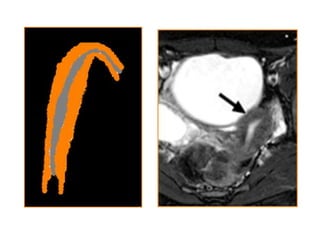

Útero unicorne

 Representa el 20%

 Se produce por un fallo en el crecimiento de uno

de los conductos de Müller

 Se presenta como útero unicorne aislado (35 %) o

asociado a un útero rudimentario

 Es frecuente la asociación con alguna

malformación renal (agenesia) ipsilateral al útero

rudimentario

 El útero rudimentario puede ser comunicante

o no y presentar o no endometrio funcional,

por lo que en ocasiones su resección está

indicada.

 El útero unicorne es curvo y elongado y se

encuentra lateralizado

 Su volumen está disminuido, siendo la

anatomía zonal normal